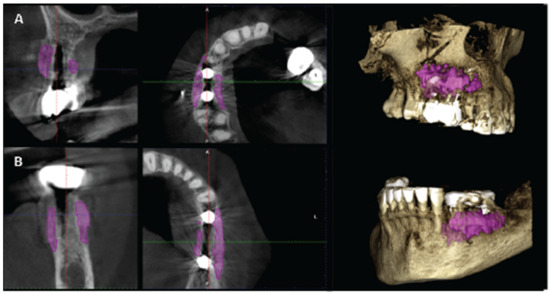

| CASE1-14 | 1 mm | 0 | 1.80 |

| 3 mm | 3.60 | 9.45 | |

| 5 mm | 5.40 | 11.10 | |